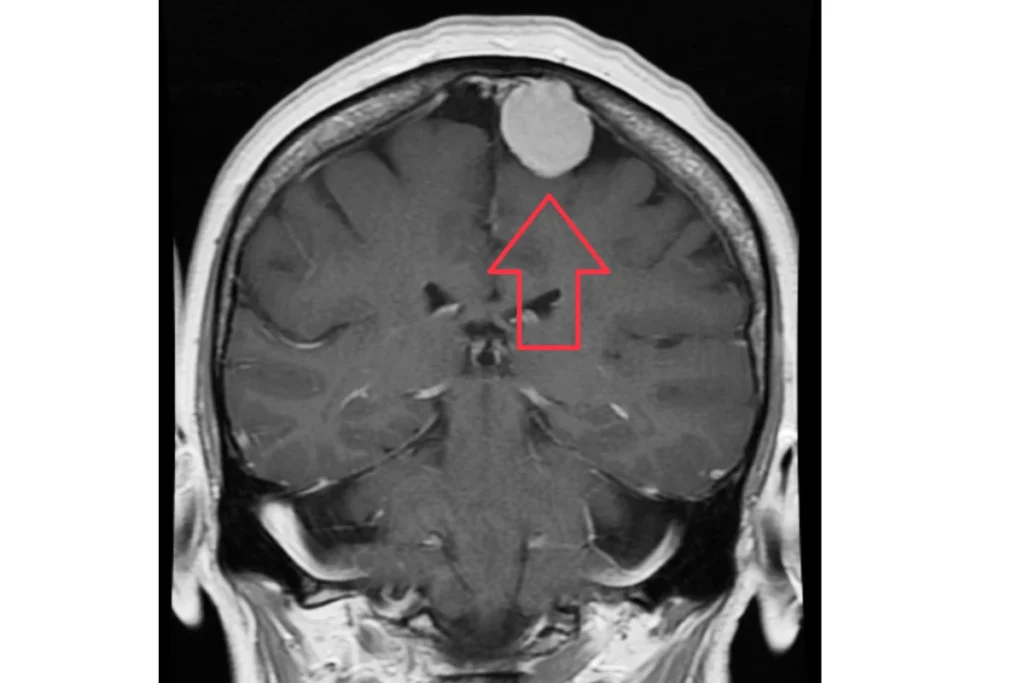

Найбільш інформативним методом діагностики менінгіоми головного мозку є магнітно-резонансна томографія (МРТ головного мозку з контрастом). Вона дозволяє побачити пухлину, оцінити її розміри, точне розташування, межі та ступінь впливу на сусідні структури. Використання контрастної речовини робить зображення ще чіткішим, оскільки менінгіоми мають характерне накопичення контрасту.

Магнітно-резонансна томографія (МРТ)